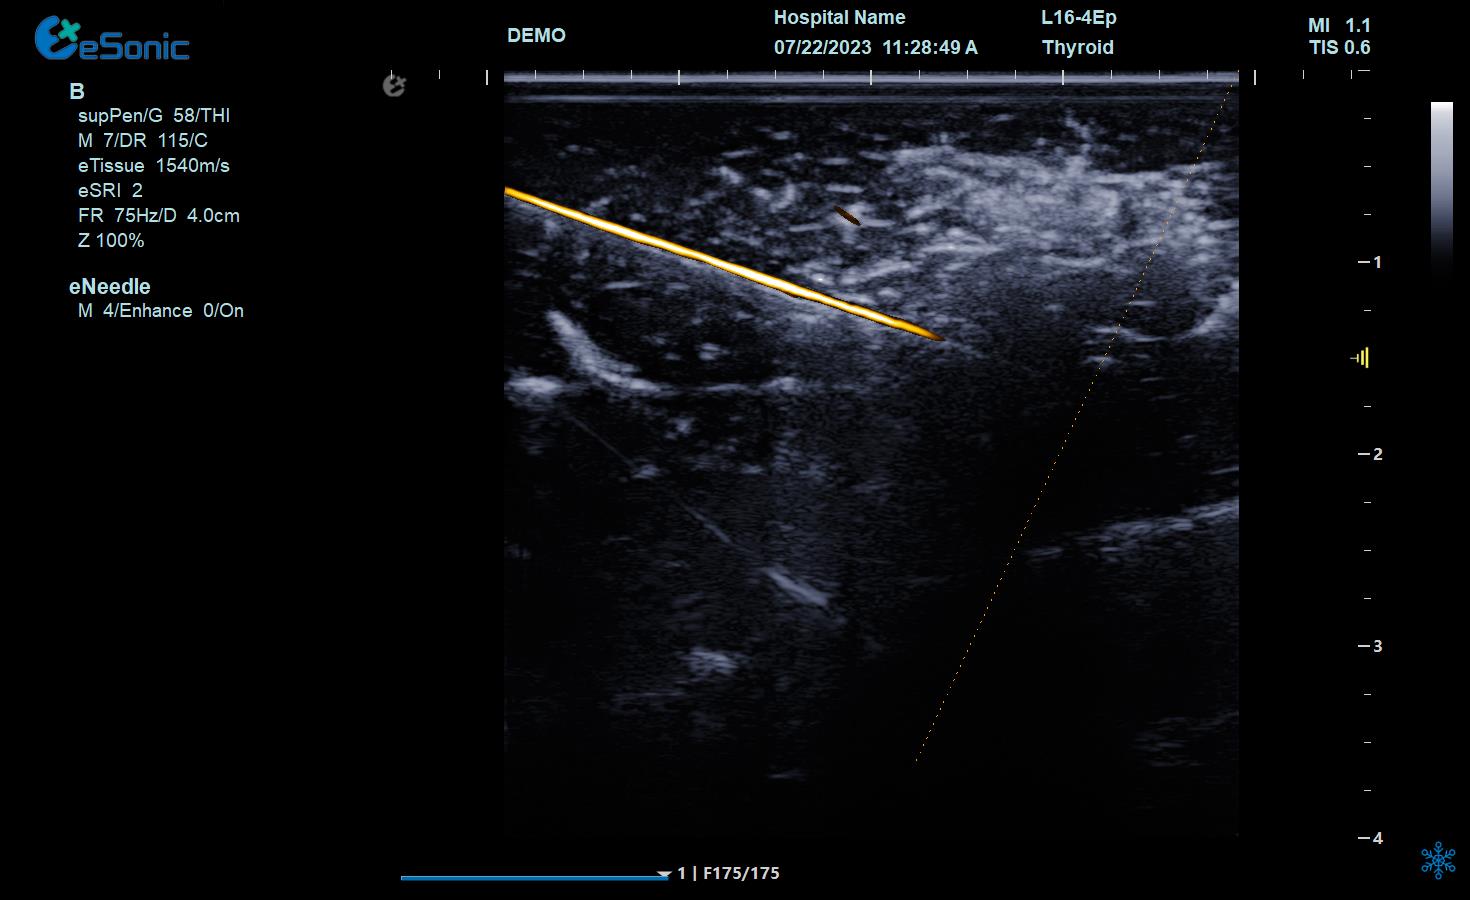

NeedleTS?穿刺针智能解决方案

?穿刺针增强显影?智能MAP?无磁导航

为临床医生有创穿刺保驾护航,真正实现精准导航。

5c8590e498a3b927e1f709e192d7ee7.png